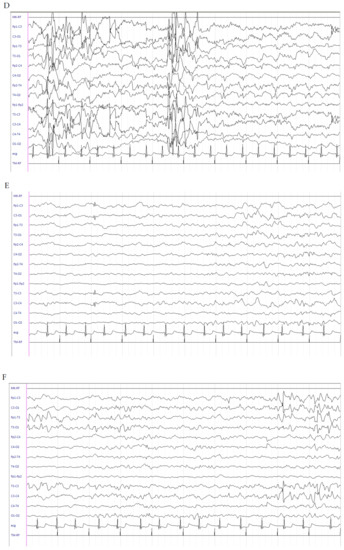

This is a male patient born at 304/7 weeks of gestational age (GA) from an unremarkable pregnancy, by emergency caesarean section (TC) due to metrorrhagia. Apgar score was 3 at 1 min and 7 at 5 min. Birth weight was 2100 g (>97th percentile). He was admitted to the Neonatal Intensive Care Unit (NICU) with immediate start of noninvasive ventilatory support; however, due to worsening of respiratory conditions, he was intubated and treated with surfactant. Seizures occurred at 3 days old and were characterized by clonic jerks at the lower right limb, often spreading to the right hand and to the counter-lateral limbs, recurring at least 1–2 times/h and lasting for about one minute. Sleeping electroencephalogram (EEG) activity showed an interictal pattern characterized by onset of high-voltage delta waves in left frontal regions, suddenly spreading to the counter-lateral homologous regions (Figure 1A) and subsequent generalization, followed by medium–high-voltage delta waves in bilateral centrotemporal regions (Figure 1B). Interictal neurological examination showed severe diffuse hypotonia and extremely poor general movements. Intravenous (IV) levetiracetam (LEV) (40 mg/kg) as a bolus was administered with only a partial reduction of seizures (occurrence once every 1–2 h). LEV was continued with a maintenance dose of 10 mg/kg/dose three times daily. Pyridoxine as a bolus (100 mg/day) was administered. Due to the seizures persisting, PB (20 mg/kg) as a bolus was administered with transient seizure disappearance; however, they relapsed after 3 h. IV infusion with midazolam was started and uptitrated to 2 μg/kg/min with poor results. Sleeping EEGs were serially performed and showed persistence of electric seizures without relevant clinical manifestations. Cranial ultrasound (CUS) scan failed to detect brain abnormalities. Brain MRI scan was performed, showing eccentric venous thrombosis at the superior right sagittal and left transverse sinuses. Low-molecular-weight heparin (LMWH) therapy was started at a dosage of 150 IU/kg every 12 h [5] with associated folic acid supplementation (100 mcg/day). LEV (60 mg/day) was continued. Pyridoxine (100 mg/day) was suspended due to lack of efficacy. At this time, hydrocortisone (5 mg/kg/day) was started with subsequent clinical and electrical seizure disappearance after 2 days. Interictal EEG abnormalities also disappeared. Brain MRI scan was repeated at days 16 and 27 and showed a regular flow signal in the context of the venous sinuses. LMWH was discontinued. Hydrocortisone was downtitrated 1 mg/kg/day every 3 days up to withdrawal at the corrected age (CA) of 35 + 4 weeks. Continuous IV administration of midazolam was gradually withdrawn. At the time of hospital discharge, the baby was seizure-free and a slight improvement in axial tone was noticed at neurological examination. LEV of 7 mg/kg/dose three times daily was continued. At the follow-up, the patient was evaluated at 38 weeks (CA), where he was seizure-free and thus LEV was downtitrated. A further improvement in axial tone with more variable and complex general movements were evidenced. At the last visit, at 44 weeks CA, the patient was still seizure-free and only showed a mild axial hypotonia with slight hypertonia at the lower limbs. The EEG showed background activity mainly characterized by medium–low-voltage theta rhythms (Figure 1C). A further brain MRI scan was normal. LEV was withdrawn.

Figure 1.

Electroencephalogram (EEG) of patient 1. (A) Interictal pattern characterized by onset of high-voltage delta waves in left frontal regions, suddenly spreading to the counter-lateral homologous regions, and (B) subsequent generalization, followed by medium–high-voltage delta waves in bilateral centrotemporal regions. (C) Background activity mainly characterized by medium–low-voltage theta rhythms.